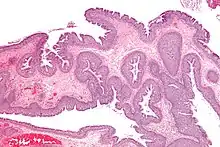

La polypose nasosinusienne (PNS) ou naso-sinusienne, plus simplement appelée polypose nasale, est une maladie affectant les sinus de la face. C'est une maladie inflammatoire chronique. Elle se traduit par une congestion des muqueuses nasales et sinusiennes : pour des raisons mal connues qui peuvent être liées à une allergie, la muqueuse des sinus s'épaissit par multiplication anormale de cellules (comme dans la maladie asthmatique), pouvant entraîner selon le stade évolutif une gêne respiratoire, voire une perte d'odorat (anosmie) si la fente olfactive est atteinte. De multiples polypes peuvent apparaître, réalisant de véritables grappes muqueuses se développant dans les cavités nasales.

Une endoscopie ou un examen clinique du nez (rhinoscopie) permet le plus souvent de diagnostiquer la PNS. Le scanner des sinus a l’intérêt d'en préciser la topographie. L’examen montre le plus souvent des polypes bilatéraux et congestionnés, accompagnés parfois d’infections. Les polypes ont l’aspect de grappes de raisins blancs. Suivant leur taille ils peuvent gêner la ventilation nasale jusqu'à entrainer une obstruction totale avec blocage de l'écoulement des mucosités, favorisant ainsi la surinfection.